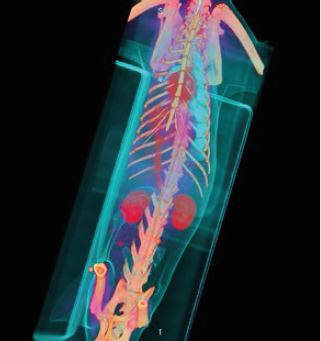

Встановлення нового стандарту у візуалізації

Global Illumination - це нова революційна технологія 3D/4D рендерингу, яка допомагає створити більш фотореалістичне зображення анатомії. Редагуйте, сегментуйте та фіксуйте фотореалістичні

зображення для покращення лікування пацієнтів та передопераційного планування.